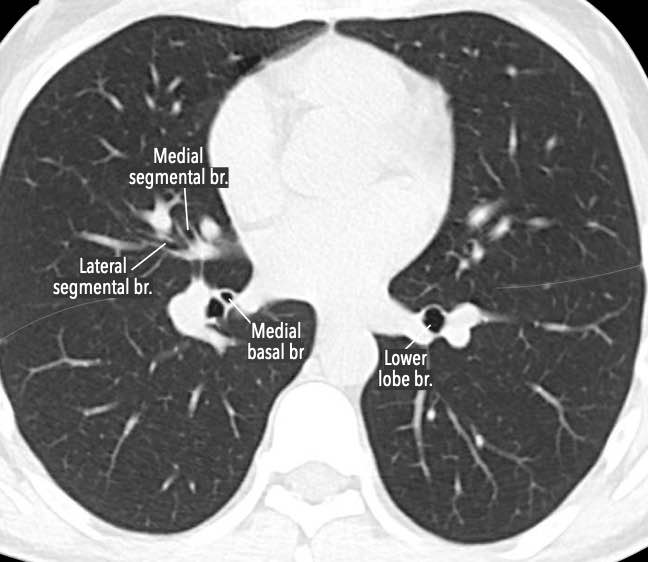

Phế quản trên CT

Cuộn qua các hình ảnh để quan sát khí quản phân chia thành phế quản chính phải và trái, sau đó tiếp tục phân chia thành các phế quản thùy và phế quản phân thùy.